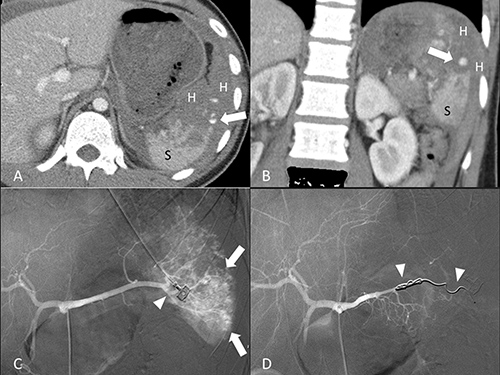

Figure 3: 19-year-old male of grade IV splenic injury underwent combined transcatheter arterial embolization. (A, B) Contrast-enhanced axial and coronal CT at portal venous phase shows a pseudoaneurysm (arrow) at the lacerated spleen (S) surrounded by hemoperitoneum (H). (C) Angiography discloses multiple tiny pseudoaneurysms (arrow) and the supplying branch artery (arrowhead). (D) Angiography after a successful combined embolization shows deployment of metallic coils (arrowheads) at the branch artery and main splenic artery distal to the dorsal pancreatic artery.